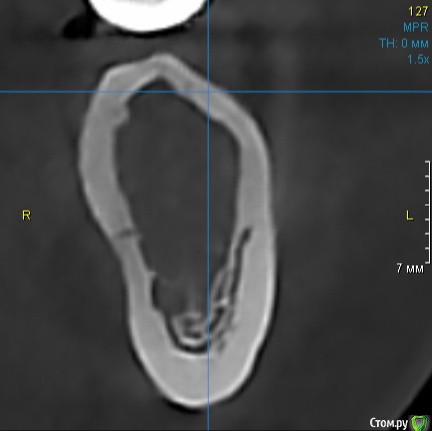

Dman Опубликовано 16 сентября, 2019 Поделиться Опубликовано 16 сентября, 2019 Девушка 30 лет, зубы были удалены в 17.На кт губка отсутствует практически в 0, какую тактику бы выбрали вы? ПС. очень неудобно что нельзя в поиск вбить "д4" - не ищет(( Ссылка на комментарий

Dman Опубликовано 18 сентября, 2019 Автор Поделиться Опубликовано 18 сентября, 2019 А другие участки кт? Все так же? да, в области отсутствующих 36, 37 вся кость такого вида Ссылка на комментарий

Astronaft Опубликовано 20 сентября, 2019 Поделиться Опубликовано 20 сентября, 2019 Это характерная картина "кавитации". Если читаете на английском: Neuralgia-inducing cavitational osteonecrosisЕсли по-простому, то это незажившая кость, скорее всего в результате ишемии. Я делал биопсию такого очага. Сравнивал с результами других докторов. Всегда похожая картина: недифференцированные клетки соединительной ткани, очаги грануляций. Если цель поставить имплант: стабилизироваться в кортикалке, ставить формик, под нагрузкой постепенно сформируются трабекулы вокруг импланта. Если заживить очаг: раскрыться, откюретажить все, добиться что бы хорошо кровило и дать 3-4 месяца. 6 Ссылка на комментарий